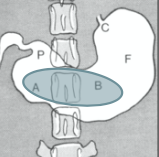

Nommez les structures de l’estomac représentées par les lettres. Est-ce un estomac de chat ou de chien?

C : cardia

F : fundus

B : corps

P : pylore

A : antre pylorique

=> estomac de chien